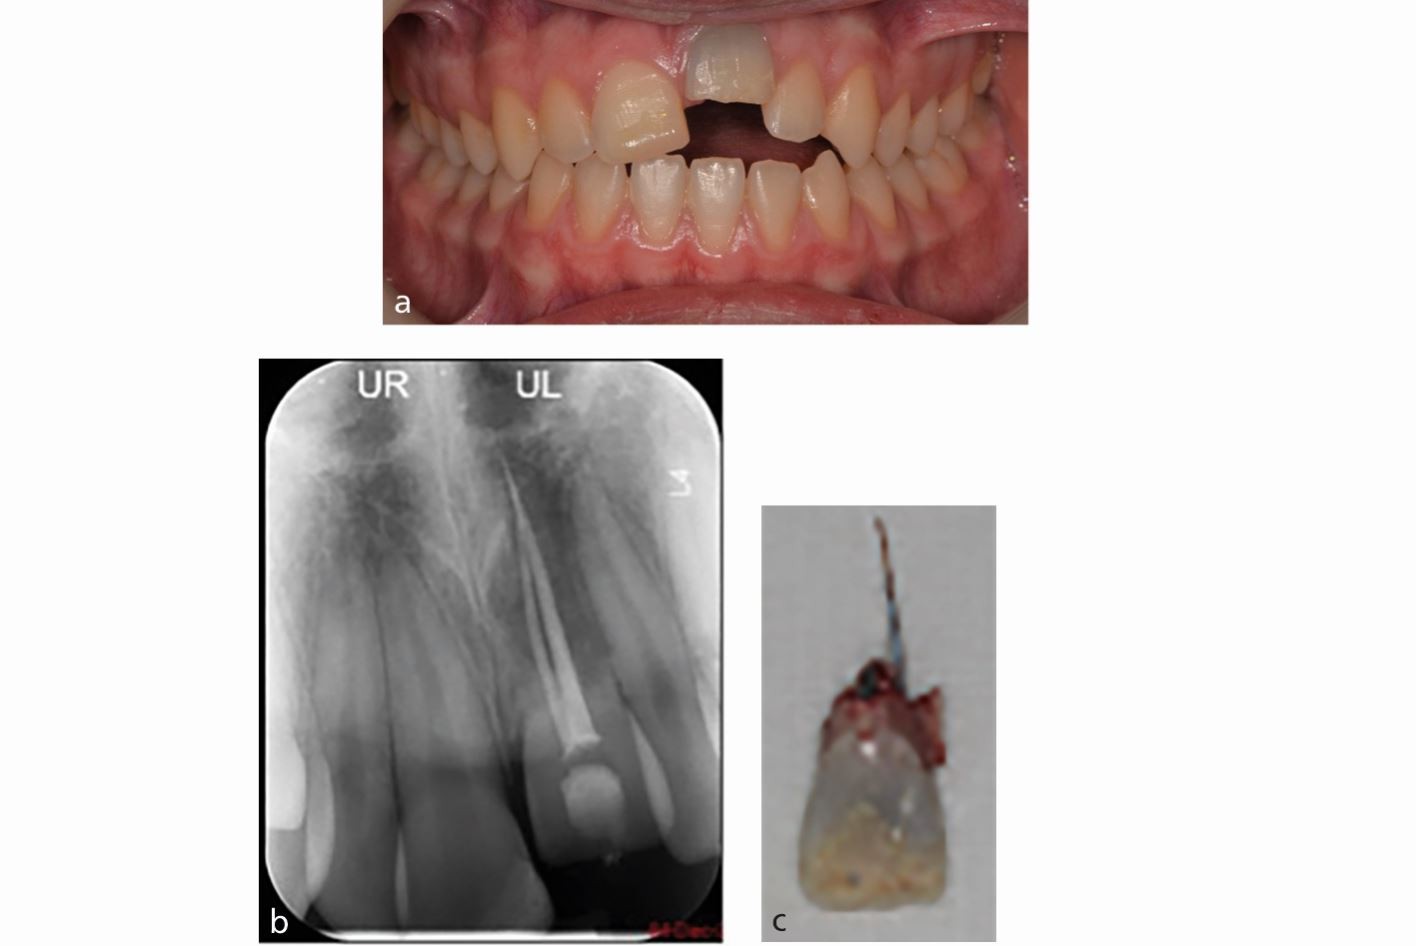

a, b, c) Late presentation of replacement-related resorption and infraocclusion of the 21 in a growing child during the COVID-19 pandemic